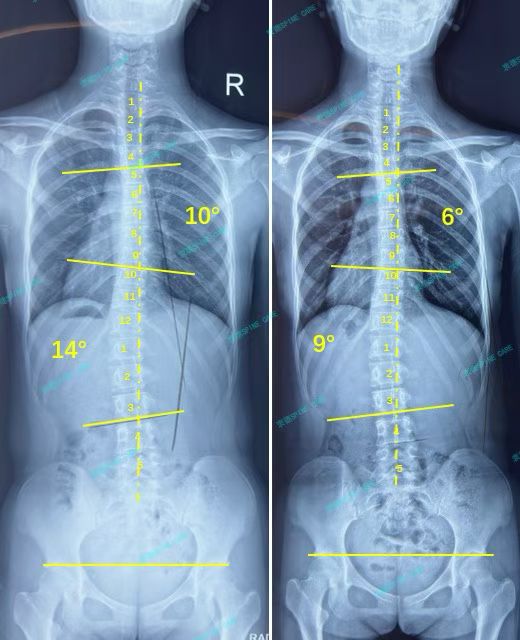

我是乐乐,下肢不等长引起的14度腰弯,ZDT训练矫正后降至9度,效果满意~

案例主人:乐乐 发现侧弯年龄:13岁 侧弯情况:Cobb角度14度

最近拍片发现我的角度从14度降到了9度,我很高兴,坚持真的非常重要!我的体态也看起来好多了。现在我的下肢长度基本一致,已经不用再继续垫鞋垫了。

Recent imaging revealed a reduction in my viewing angle from 14 degrees to 9 degrees, which I find gratifying. Maintaining this posture is indeed crucial! My posture has also significantly improved. Currently, the length of my lower limbs is essentially uniform, eliminating the need for continued use of insoles.